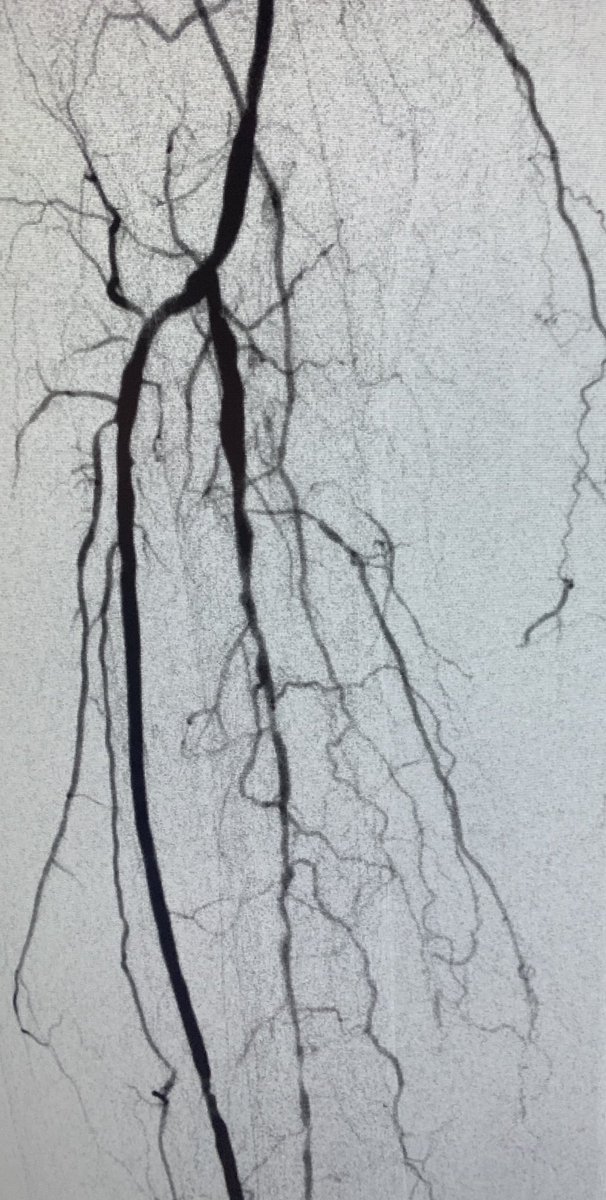

Active R4 patient limited at her full time job, losing sleep at night. Motivated to fight through pain, but needs help. Amazed at how well she functioned like this. She'll do awesome now! Shout out to @keithppereira for the support during the case! #CLIFighters #MyLegMyLife

Watts_IR's tweet image. Active R4 patient limited at her full time job, losing sleep at night. Motivated to fight through pain, but needs help.  Amazed at how well she functioned like this.  She'll do awesome now! Shout out to @keithppereira for the support during the case! #CLIFighters #MyLegMyLife